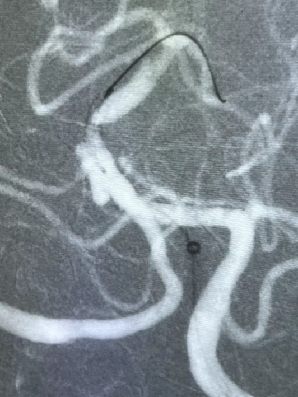

导丝怎么扩【载药时代 球扩天下】NOVA DES®颅内药物洗脱支架在颅内富穿支区域使用体会二例!_https://www.jmylbn.com_新闻资讯_第30张

DSA

重要影像结论:基底动脉重度狭窄。